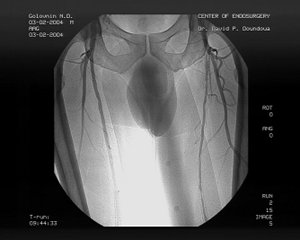

Пациент обратился вновь в клинику через 1,5 года после первичной ангиопластики и через год после повторной с перемежающейся хромотой слева через 400м, правая нк не беспокоила. Пациент также обратил внимание на умеренный отек левой стопы. ЛПИ слева составил 0,64. Вновь проведена ангиография, на этот раз трансрадиальным доступом, выявлены рестенозы внутри стентов в устье левой ПБА, рестеноз в средней порции левой ПБА, где стентирование не проводилось, рестеноз внутри проксимального стента в Гунтеровом канале. Правая нижняя конечность оставалась без гемодинамически значимых изменений. Обнаружен артериовенозный сброс в левой нижней конечности из подколенной артерии в одноименную вену. (см. рис. 4а и 4б)

![]() |

|

| Рис. 4а Контрольная ангиография через 18 мес. Радиальный доступ. | Рис. 4б Дооперационная ангиография через 18 месяцев с артерио-венозным сбросом. Доступ через подколенную артерию |